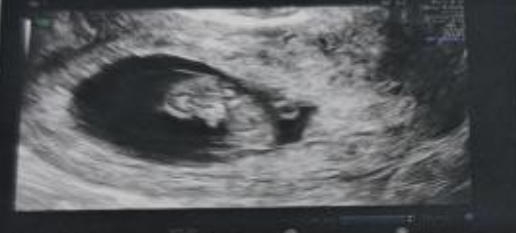

2025年6月,进行复苏冷冻胚胎移植,一次验得好孕并顺利“毕业”。